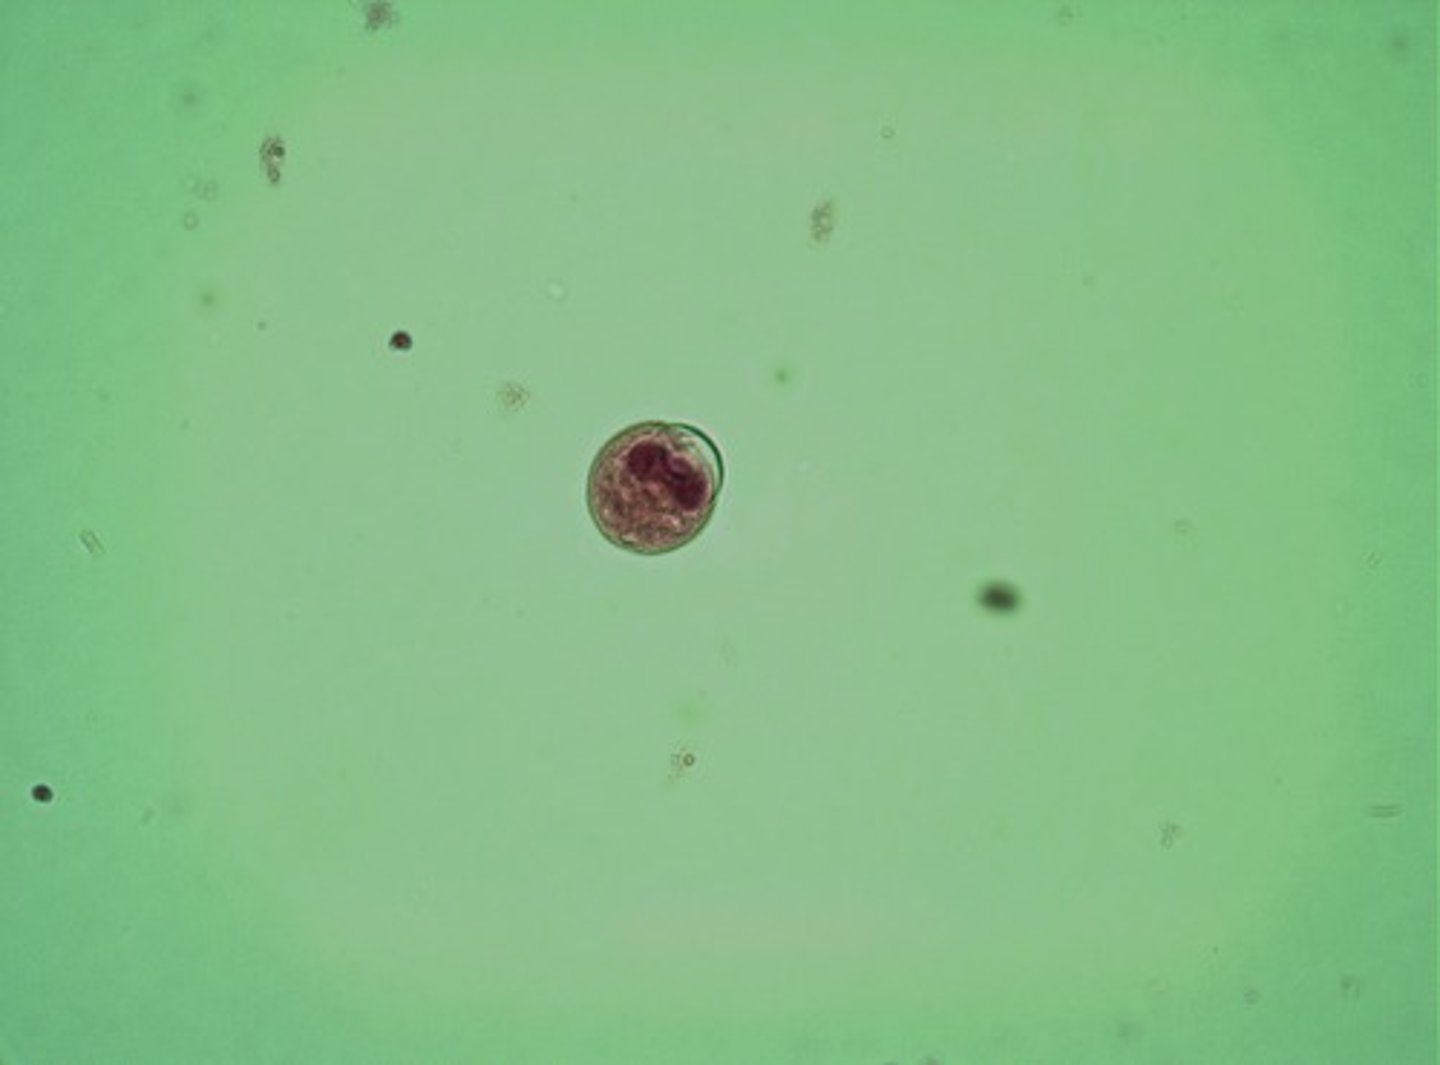

Entamoeba histolytica cyst

Infection by ingestion of cysts in contaminated drinking water

- causes diarrhea, dysentery and liver abscess

- has chromatid bar

Dx: fexal exam/serological test

Entamoeba histolytica cyst pic2